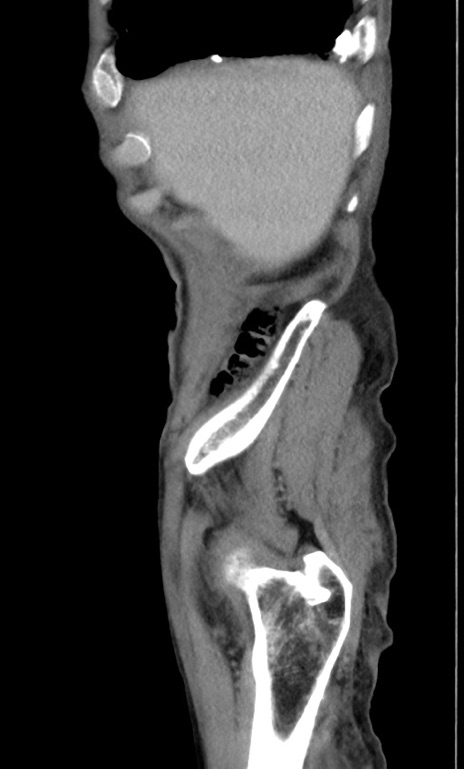

症例3(矢状断像)

【症例】 70歳代男性

【主訴】右鼠径部腫瘤、疼痛

【現病歴】本日朝より上記主訴あり、受診。

【既往歴】膀胱癌にて膀胱全摘、両側尿管皮膚瘻

【データ】WBC 5600、CRP 0.56